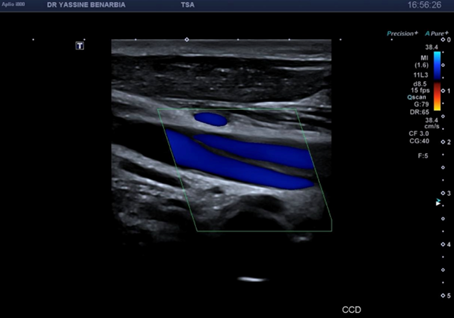

Du côté droit, l'examen met en évidence une dissection du tronc brachiocéphalique (TABC) avec présence d'un faux chenal circulant. Le flap intimal est clairement visible en mode B, séparant le vrai chenal du faux chenal. Au Doppler couleur, on observe un double flux avec des vélocités différenciées : le vrai chenal présente un flux rapide (codé en bleu qui s’éloigne de la sonde) tandis que le faux chenal montre un flux plus lent (codé en rouge qui se rapproche de la sonde).

Les signes retrouvés à l'échographie-Doppler sont : flap intimal mobile visible en mode B séparant vrai et faux chenal, double lumière artérielle en coupe transversale et longitudinale, flux différenciés au Doppler couleur (vélocités élevées dans le vrai chenal, flux plus lent dans le faux chenal), et spectre Doppler pulsé conservé dans le vrai chenal (triphasique ou biphasique).

Le faux chenal peut être circulant (flux présent, comme dans notre cas) ou thrombosé (sans flux). Un faux chenal circulant stable sans sténose hémodynamique est de bon pronostic sous surveillance.